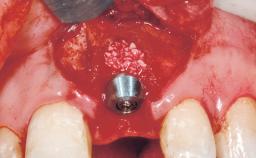

Immediate Flapless Placement of an Implant in a Maxillary Right Lateral Incisor Site

This 43-year-old male patient, a non-smoker, came to our practice because of a fracture of tooth 12 caused by a bicycle accident. Due to the combined para- and infrabony crown and root fracture, tooth extraction, and subsequent implant placement were suggested to the patient as the therapy of choice. The patient had high esthetic expectations with regard to the treatment outcome and asked for an immediate fixed provisional restoration. His individual esthetic risk profile summed up to a medium esthetic risk.